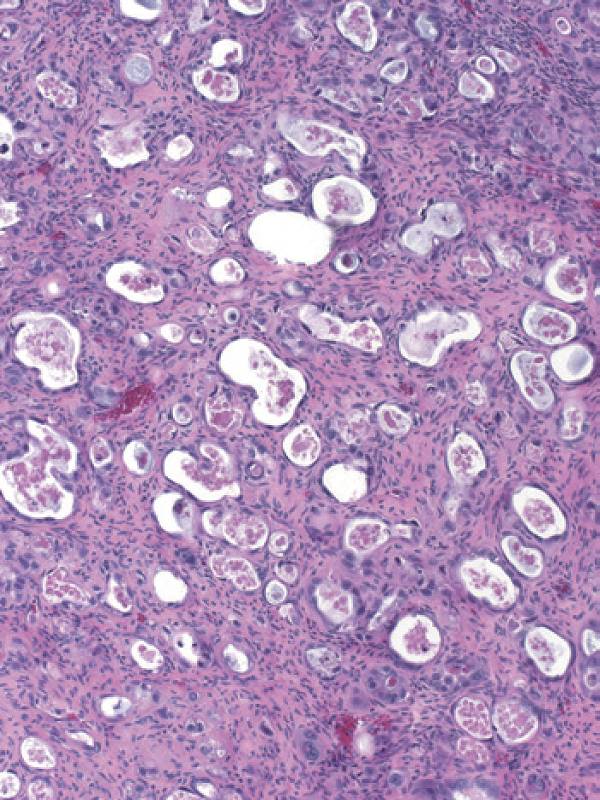

彩图4-3 卵巢透明细胞癌

乳头状结构中基质玻璃样变是许多透明细胞癌乳头中的典型特征

彩图4-4 典型混合细胞类型卵巢透明细胞癌,少量管状囊性结构(右上)与大量含透明细胞质的细胞结节样生长共存(左下)